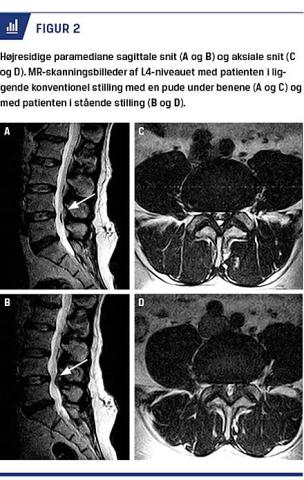

I stående stilling så man bilateralt hypertrofiske ligamenta flava, der protruderede ind i durasækken og gav tiltagende forsnævring af recesserne med kløverbladskonfiguration på de aksiale snit – specielt ud for L4/L5-niveauet (Figur 2). Durasækkens tværsnitsareal blev reduceret fra 112 mm2 til 71 mm2, hvilket medførte høj afklemning af højre L5- og S1-rod inden deres neuroforaminære afgang fra spinalkanalen. Efter et halvt år med forgæves konservativ behandling blev der derfor foretaget dekompression af recesserne ved laminektomi på både L4/L5- og L5/S1-niveau. Patienten havde efter operationen bedring af de stillingsbetingede symptomer, men fik desværre en stor reprolaps på L5/S1-niveauet et halvt år efter den ellers vellykkede reoperationen.